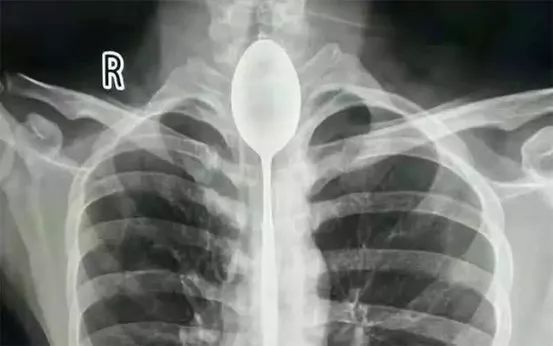

勺子卡食道一年

新疆煤矿总医院

2017年,20岁出头的张先生与他人喝酒打赌,冲动之下,将20厘米长的钢勺吞进肚里,勺头卡在了食道狭窄处。一年的时间里,张先生觉得并无大碍没有去医院将钢勺取出。

直到今年10月下旬,张先生被人在胸口打了一拳,感觉自己胸部疼痛、憋气、呼吸不畅,才去医院就诊。10月22日,新疆煤矿总医院的三位医生共同合作,冒着食道撕裂、穿孔、大出血、纵隔感染的风险,最终将钢勺顺利取出,为张先生免去了开胸取勺之痛。随后张先生顺利出院。